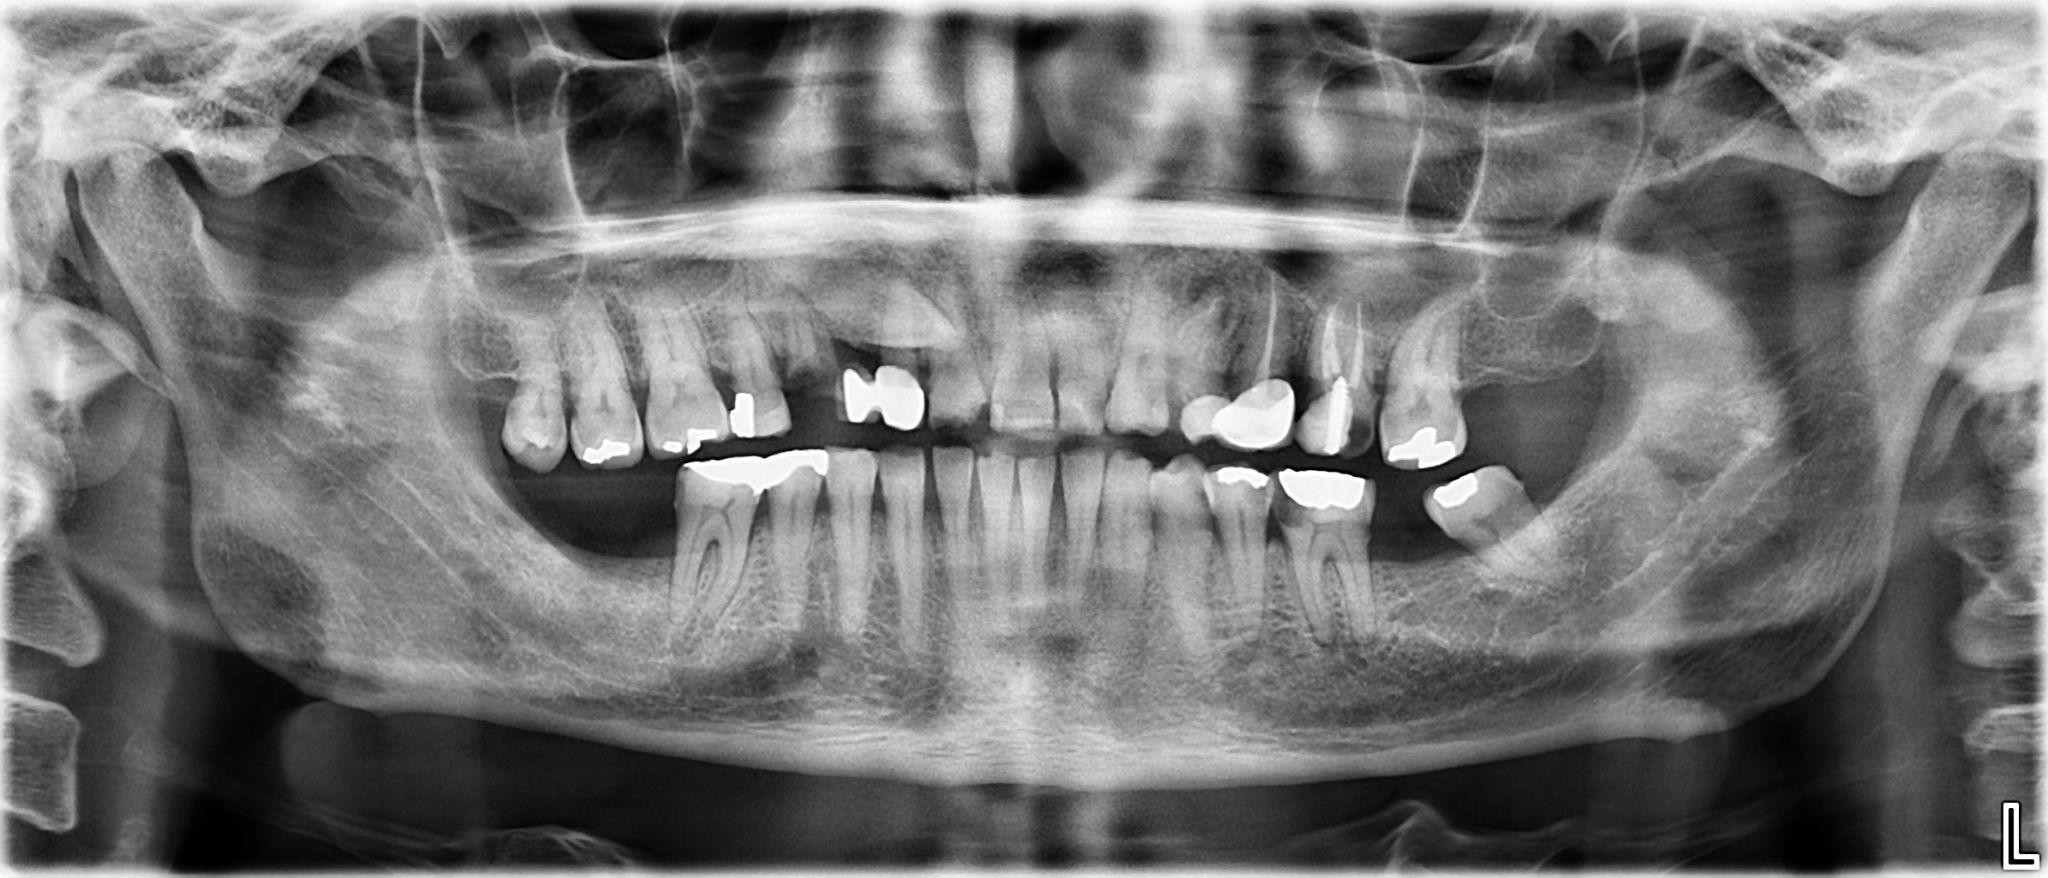

9. What options can be selected for the first quadrant of this panoramic X ray?

10. What options can be selected for the second quadrant of this panoramic X ray?

11. What options can be selected for the third quadrant of this panoramic X ray?

12. What options can be selected for the forth quadrant of this panoramic X ray?